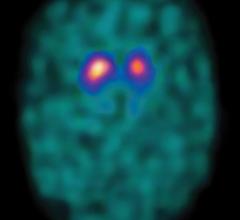

July 5, 2011 – The first radiopharmaceutical imaging agent to help physicians evaluate patients with suspected Parkinsonian syndromes (PS), such as Parkinson’s disease (PD), has been cleared by the U.S. Food and Drug Administration (FDA). GE Healthcare’s DaTscan (Ioflupane I 123 Injection) gives physicians diagnostic capability that may lead to timely, appropriate treatments for suspected PS patients.